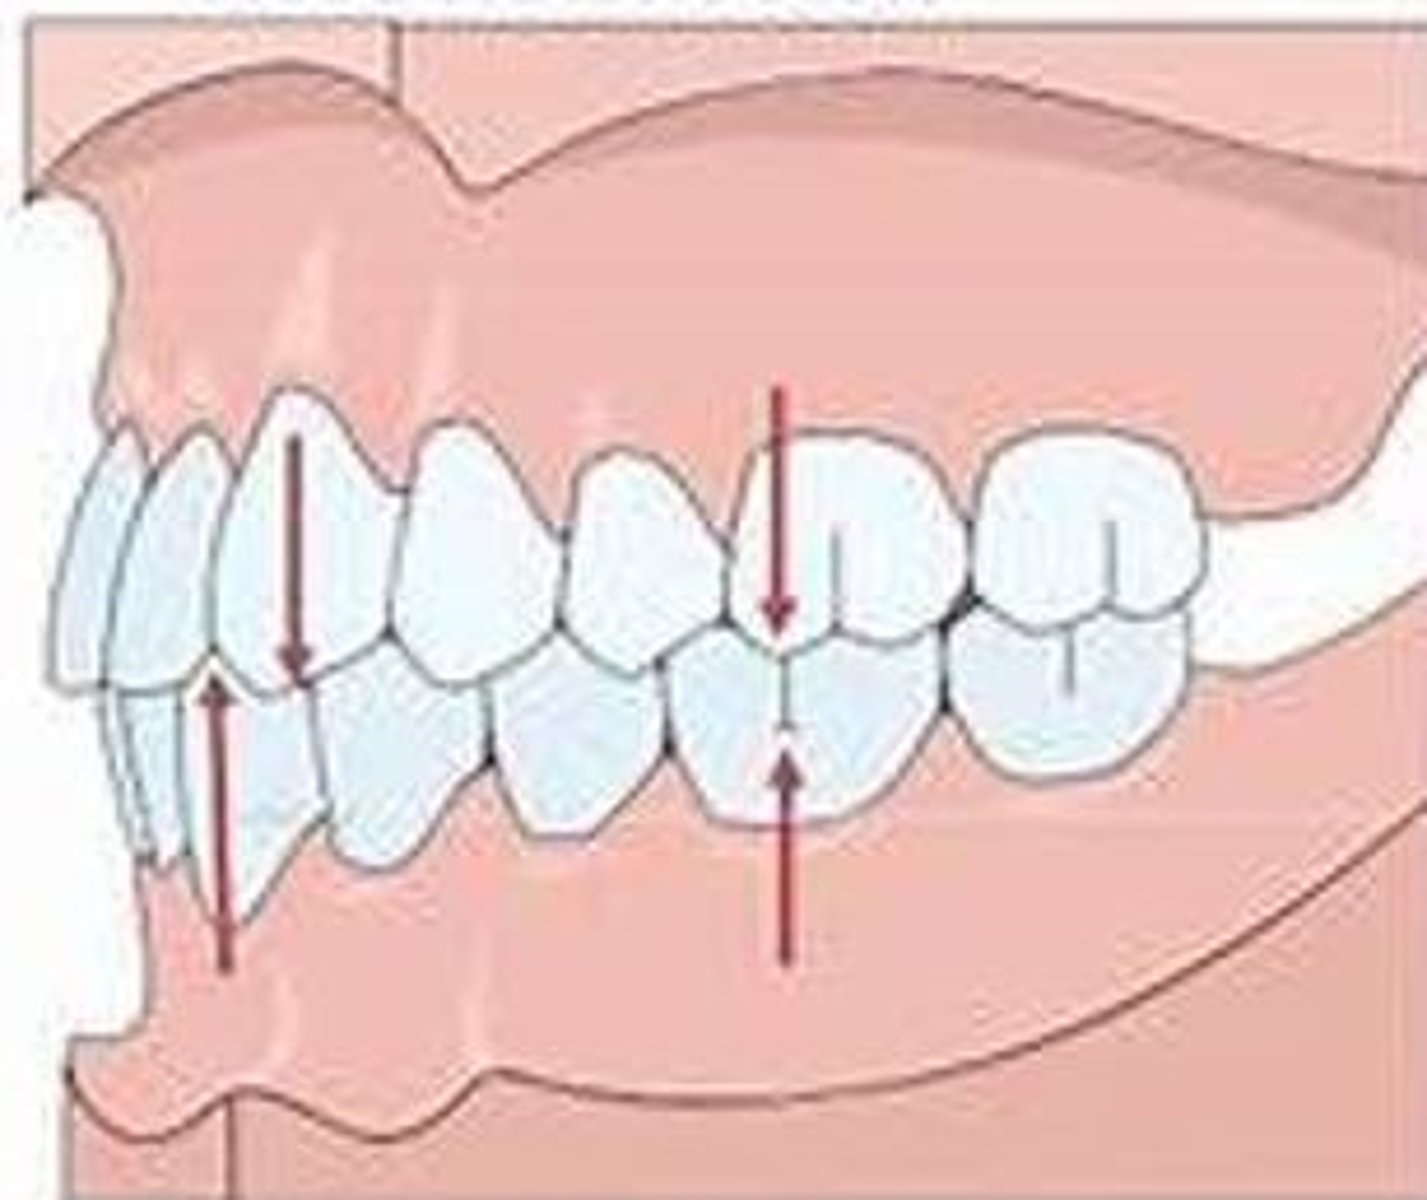

Class I occlusion

When the mesiobuccal cusp of the maxillary first molar occludes with the mesiobuccal groove of the mandibular first molar it is called Angle Class ___ occlusion.

<p>When the mesiobuccal cusp of the maxillary first molar occludes with the mesiobuccal groove of the mandibular first molar it is called Angle Class ___ occlusion.</p>